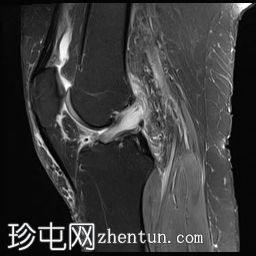

轴位T2加权三维增强像 (T2-ME3D-WE)

6.jpg

前交叉韧带 (ACL) 呈增厚的高信号,提示黏液样变性。然而,纤维仍保持连续性,在矢状位质子密度加权像上尤为明显。这种特征性表现类似于芹菜,因此被称为“芹菜茎征”。

内侧半月板后角显示异常信号,延伸至关节面下方,符合3级撕裂。

髌股关节和胫股关节均可见骨关节炎改变,表现为骨赘形成、胫骨棘突增生以及关节软骨在相对关节面上的剥脱。

可见少量滑液积液,滑液内可见髌上皱襞。

内侧副韧带可见异常水肿信号,但未见纤维断裂,提示为I级扭伤。

此外,胫股关节胫骨髁间区可见局灶性软骨变薄,伴有骨暴露和骨髓水肿。